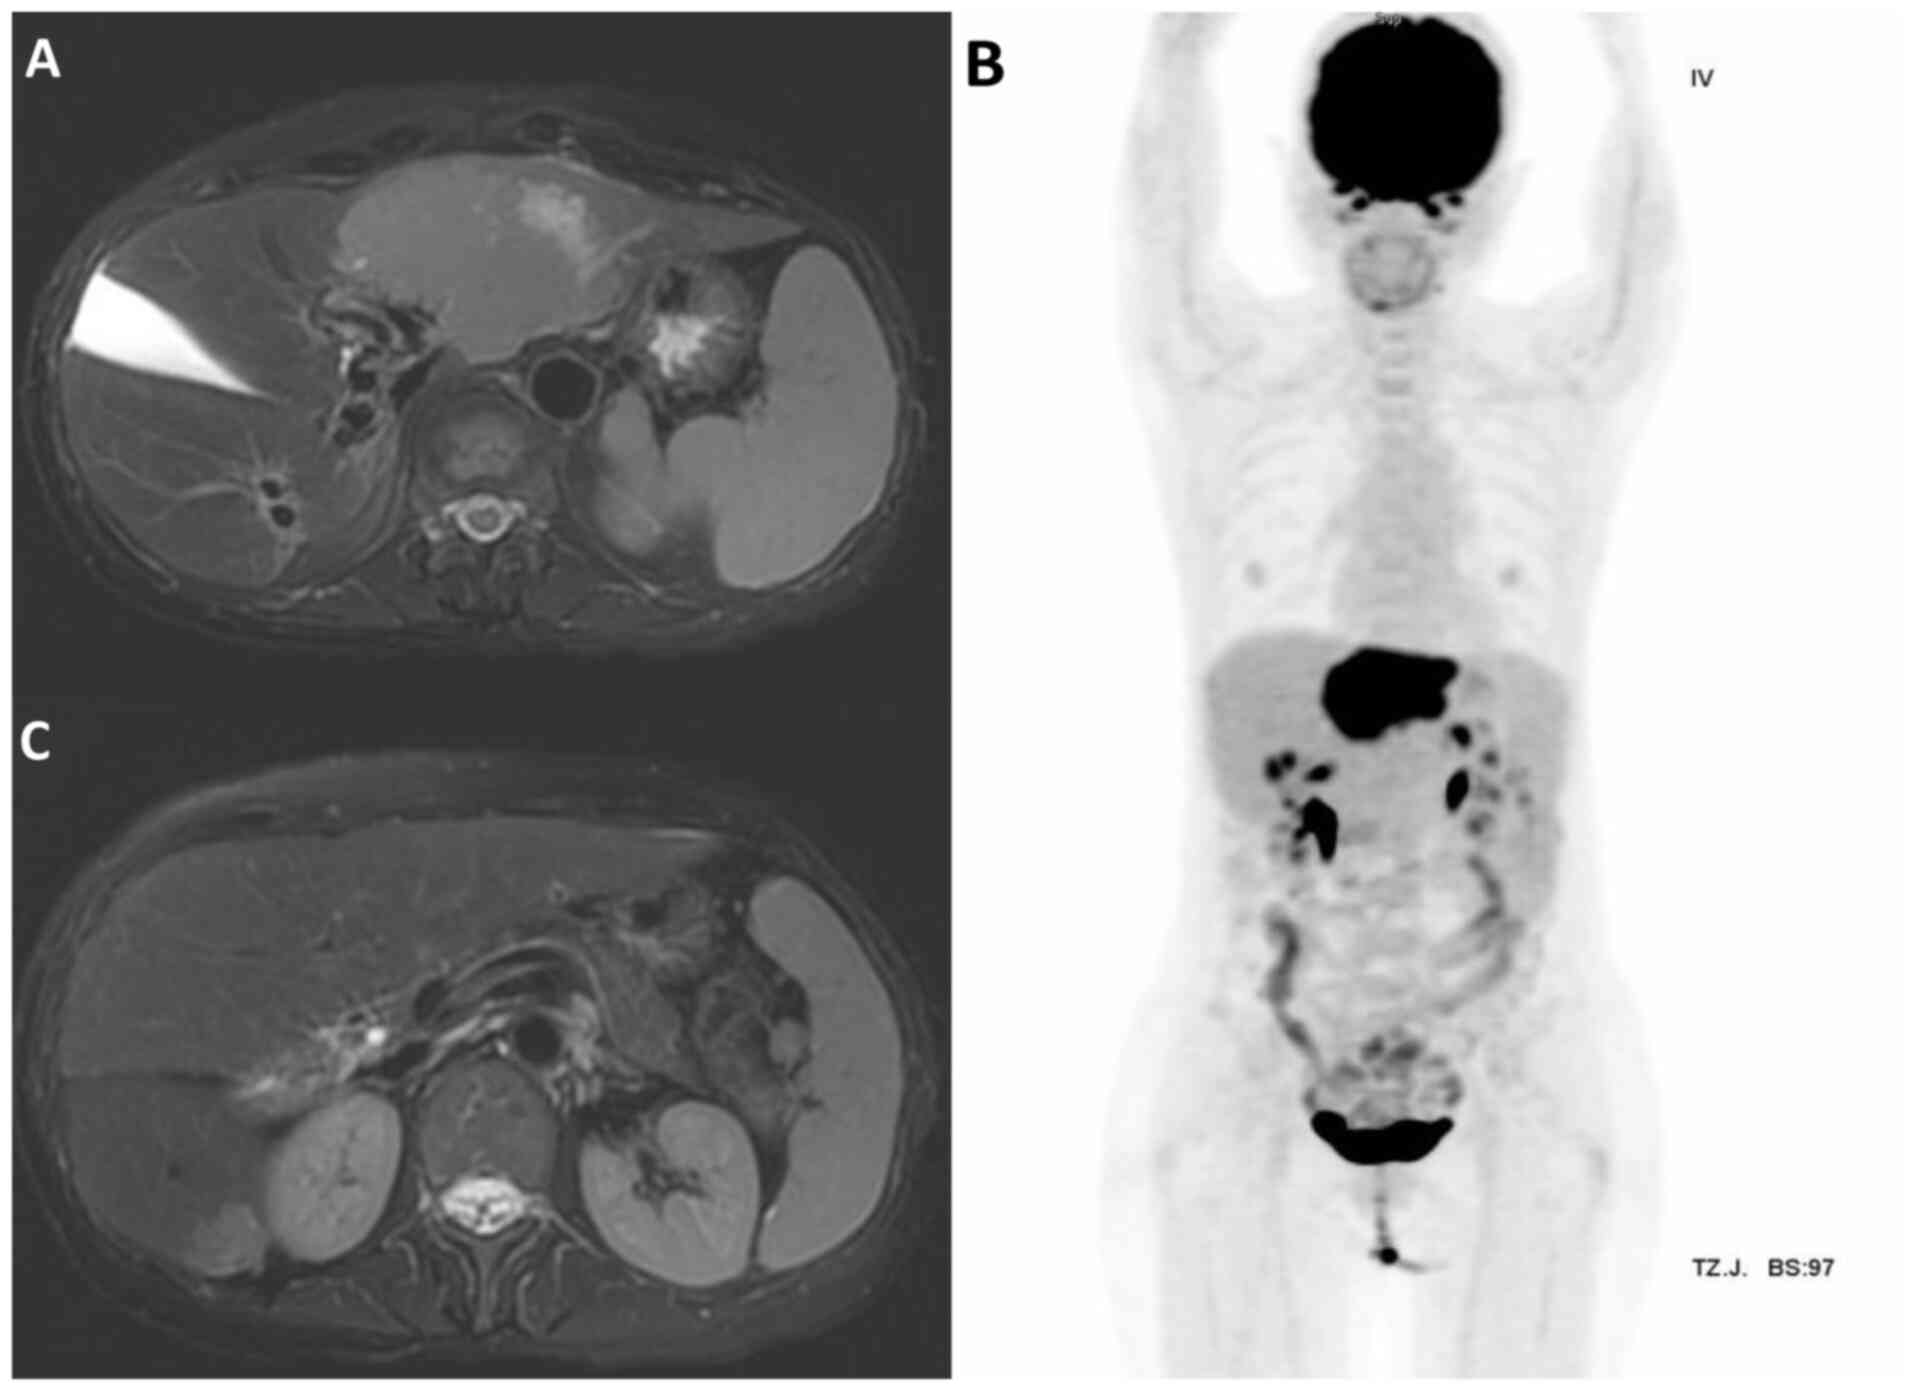

A 61-year-old woman with a history of Sjögren's syndrome, managed with hydroxychloroquine for 38 years, was diagnosed with CVID, and had been receiving intravenous immunoglobulin therapy since February 2023. In December 2023, the patient presented to the Emergency Department of Penghu Branch, Tri-Service General Hospital (Taiwan), with shortness of breath that had progressed over several days. Abdominal ultrasonography incidentally revealed two hypoechoic masses in the left lobe of the liver (Fig. 1). Subsequent dynamic abdominal computed tomography (CT) revealed two hypo-enhanced lesions located in liver segments 2/4a and 6 (Fig. 2), which were initially misdiagnosed as hepatocellular carcinoma due to their non-specific radiological features. The patient's tumor markers, including α-fetoprotein and carbohydrate antigen 19-9, were within normal limits. Additionally, liver function tests, including those for alanine aminotransferase (76 U/l; normal range, 7–56 U/l), aspartate aminotransferase (56 U/l; normal range, 10–40 U/l) and alkaline phosphatase (277 U/l; normal range, 44–147 U/l), showed mildly elevated levels, while the bilirubin levels (0.5 mg/dl; normal range, 0.1–1.2 mg/dl) remained normal. A sonography-guided liver biopsy was performed, and hepatic MZL was histologically confirmed based on strong CD20 positivity, a low Ki-67 proliferation index (~5%) and the absence of CD3 in neoplastic cells. Focal positivity for CD10 was also observed (Fig. 3). Samples were fixed in 10% neutral buffered formalin at room temperature for 24, sectioned to 4-µm and then stained with hematoxylin (room temperature for 5 min) and eosin (room temperature for 2 min), before being observed by light microscopy. For immunohistochemistry, the sections were incubated with anti-CD20 (dilution 1:100; cat. no. ab9475; Abcam), anti-CD3 (dilution 1:100; cat. no. ab16669; Abcam), anti-CD10 (dilution 1:100; cat. no. NCL-L-CD10-270; Leica Biosystems) and anti-Ki-67 (dilution 1:200; cat. no. ab16667; Abcam) primary antibodies at room temperature for 1 h and then with biotinylated secondary antibody (horseradish peroxidase-conjugated; dilution 1:200; cat. no. ab6720; Abcam) at room temperature for 30 min. Light microscopy was used for observation.

Figure 2.

Dynamic abdominal computed tomography revealing two hypo-enhanced lesions in the liver. (A) Lesion located in segment 2/4a, demonstrating hypo-enhancement on arterial phase imaging. (B) Lesion in segment 6, showing similar hypo-enhancement characteristics.

Bone marrow aspiration revealed no evidence of lymphoma. Abdominal magnetic resonance imaging (MRI) and whole-body positron emission tomography (PET) scans showed two ill-defined fluorodeoxyglucose (FDG)-avid mass lesions of 7.8 and 1.8 cm in diameter in segments 2/4a and 6 of the liver, respectively (Fig. 4), classified as stage IV disease according to the Lugano Staging System (7).

Figure 4.

Pre-involved site radiotherapy images. Magnetic resonance imaging results showing two ill-defined mass lesions measuring 7.8 and 1.8 cm in liver segments (A) 2/4a and (C) 6, respectively. (B) Positron emission tomography scan showing two ill-defined fluorodeoxyglucose-avid lesions in the liver, consistent with stage IV disease.